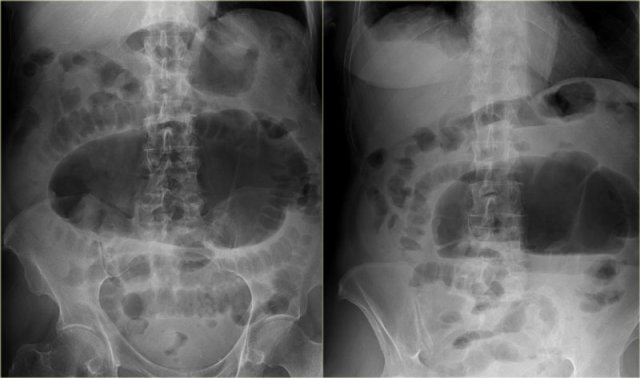

On the left a plain abdominal film is shown of a 57 year old man with a two day history of increasing abdominal pain and distension.

First look at the image and then continue.

Besides diffuse dilatation of the bowel, the major finding on this film is a large air containing structure in the pelvis.

An important diagnosis to consider would be a volvulus of the colon and many would diagnose this as a sigmoid volvulus because it is located in the pelvis.

However this actually is a cecal volvulus as will be explained below.

Cecal Volvulus

A volvulus always extends away from the area of bowel twist.

So a sigmoid volvulus can only move upwards and usually goes to the right upper quadrant.

Cecal volvulus however can go almost anywhere and can even be located in the pelvis (figure).

On the left a typical cecal volvulus is seen.

We can see the beak-like transition zone located in the right lower quadrant indicating that this is a cecal volvulus.

The dilated cecum is located in the left upper quadrant.

Also notice the collapsed descending colon posterior to the dilated cecum (curved arrow).

The x-rays show a typical cecal volvulus.

Notice that the dilated bowel points toward the area of twist, which is the area where you expect the cecum to be located.

Continue with the CT-images.

Scroll through the images.

The areas of twist and obstruction are marked.